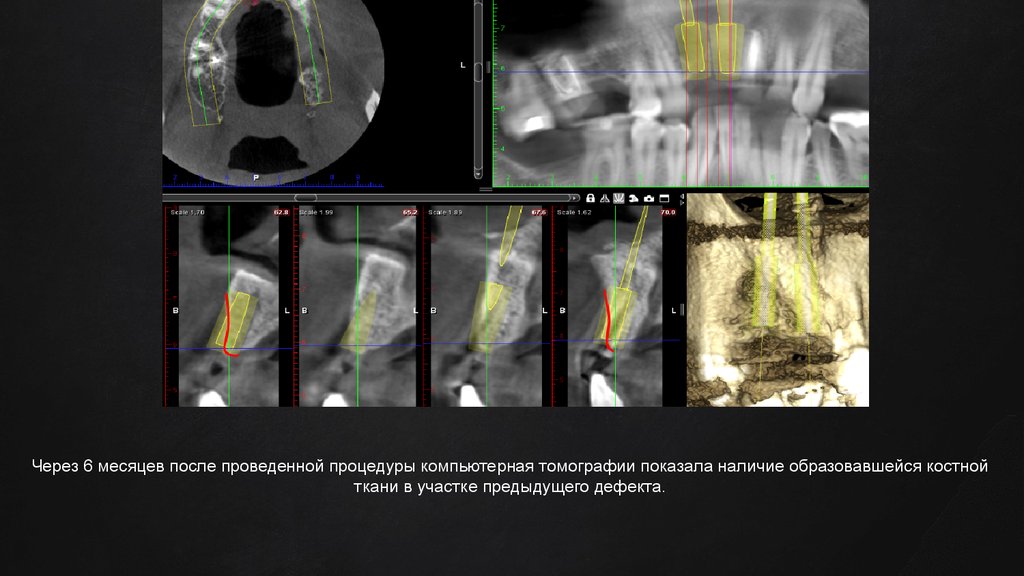

Через 6 месяцев после проведенной процедуры компьютерная томографии показала наличие образовавшейся костной

ткани в участке предыдущего дефекта.